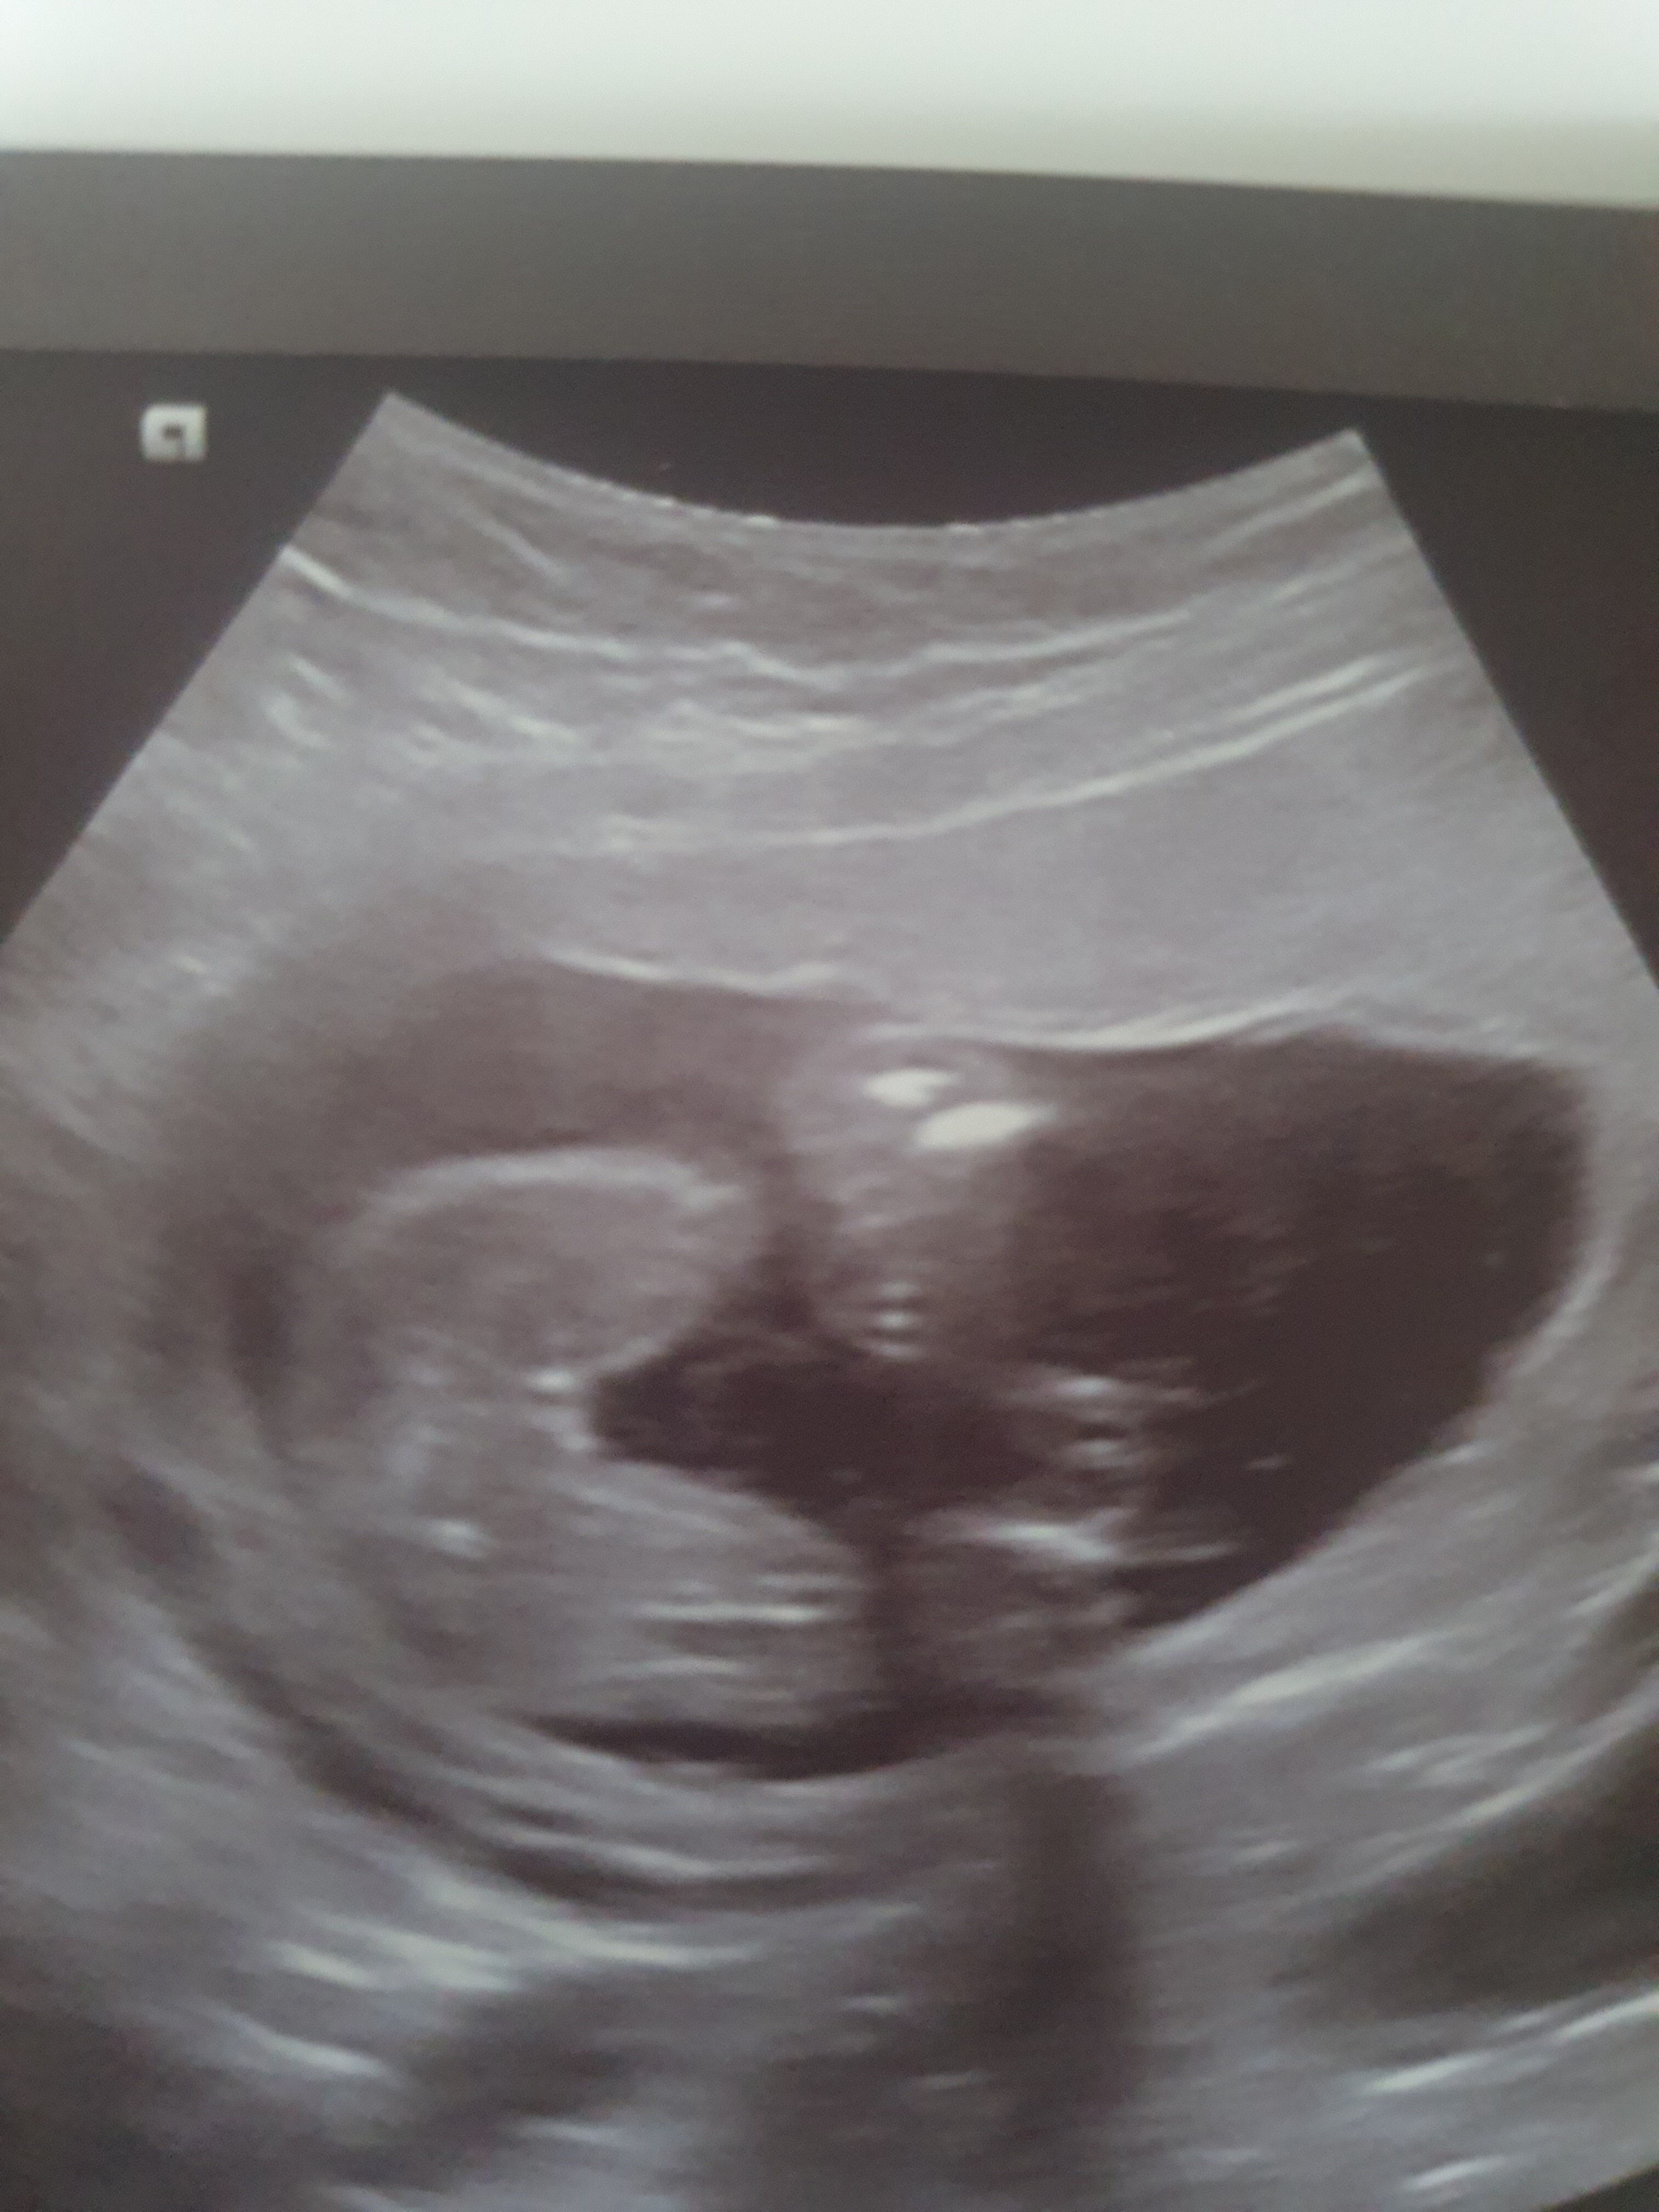

Hej dziewczyny co powiecie. Na to usg . Zaczne od tego ze to moja druga ciaza (przy corce pierwszej sie lekarz nie pomylil do samego konca a bylo to 8 lat temu) na nrz ten sam lekarz i w 14 tygodniu powiedzial mi sam ze bede miala syna. Po czym dwa tygodnie pozniej czyli do wczoraj pojechalam na usg prywatne 3d/4d i tam pani dr stwierdziła dziewczynke . Ja juz sama nie wiem zrekniecie bo ciagle nie dowierzam i ludze se na ta pierwsza wresje ze jednak bedzie synek tym razem..

Myslicie ze w tyg 15+6 na badaniu 3d/ 4d mogla sie pomylic sa jakies szanse ze jeszcze z tego bedzie chlopiec ? 😁 Dodam że gdy zapytalam czy to pewne odpowiedź brzmiala,, to zalezy na ile pani mi ufa,, no o w opisie nie opisala nic ze dziecko jest o pluci zenskiej 🤔

Mam tylko corke wiec nie mam porownania w usg dodam zdjecie corki 8 lat temu wygladalo to zupelnie inaczej i dla. Mnie bylo jasne w dodatku zaznaczyl i napisal ze napewno cora.. A tu kupe kasy wydane i ja nie jestem pewna w stu procentach po jej wypowiedziach dr byla z polecania kolezanki i dodam ze tania to nie byla bo az 370zl skasowala za samo usg ps w zalaczniku zdjecie starszej corki